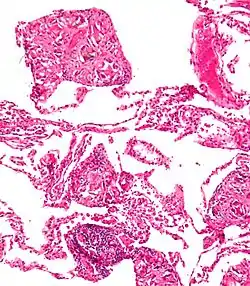

La Talcosis es una enfermedad pulmonar causada por la absorción de talco.

Se ha relacionado con silicosis resultante de la inhalación de talco y silicatos. También está ligado al consumo de heroína donde podría ser usado el talco utilizado como un adulterante para aumentar el peso en las ventas de calle, por lo que la inyección de heroína con talco diluido causa talcosis ..."[1]

La talcosis también puede surgir de la inyección de medicamentos destinados a la administración oral, como el talco está presente en muchas tabletas y cápsulas que son objeto de abuso por vía intravenosa , tales como benzodiazepinas , dextroanfetamina , y en la prescripción de narcóticos. It is one of several noted associations and possible risks of street heroin use.[2]